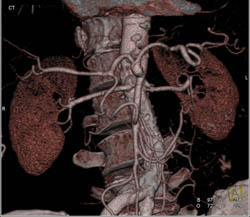

Celiac and Hepatic Artery Aneurysms in Multiple Phases